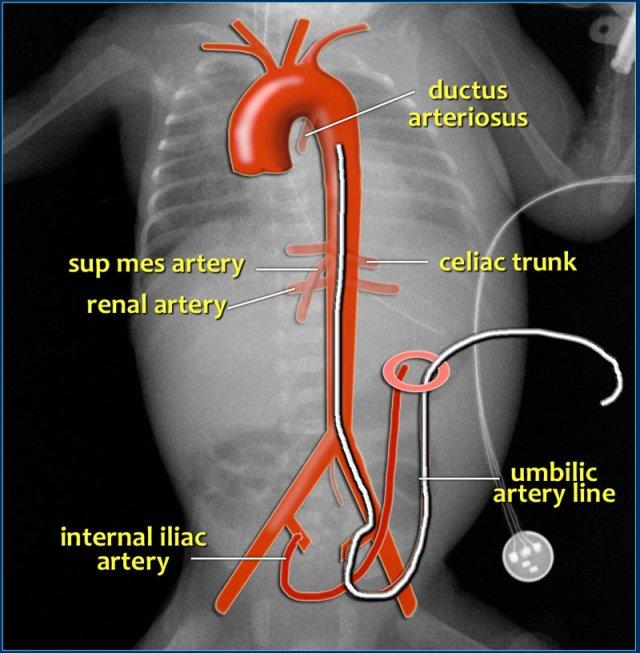

Đường truyền động mạch rốn

Đặt catheter động mạch rốn cung cấp đường vào trực tiếp hệ thống động mạch, cho phép đo huyết áp động mạch chính xác, lấy mẫu máu và tiếp cận mạch máu để truyền dịch và thuốc.

Catheter cần được luồn qua động mạch rốn và đi vào động mạch chủ qua động mạch chậu trong.

Catheter cần thể hiện vòng cung điển hình từ rốn đi xuống dưới vào động mạch chậu trong.

Để tránh đặt catheter vào các nhánh của động mạch chủ, đầu catheter cần nằm ở vị trí cao phía trên các động mạch thân tạng, mạc treo tràng và động mạch thận, hoặc ở vị trí thấp phía dưới động mạch mạc treo tràng dưới:

- Vị trí cao: T6-T9

- Vị trí thấp: L3-L5

Vị trí cao được khuyến cáo vì ít gây biến chứng mạch máu hơn (15).